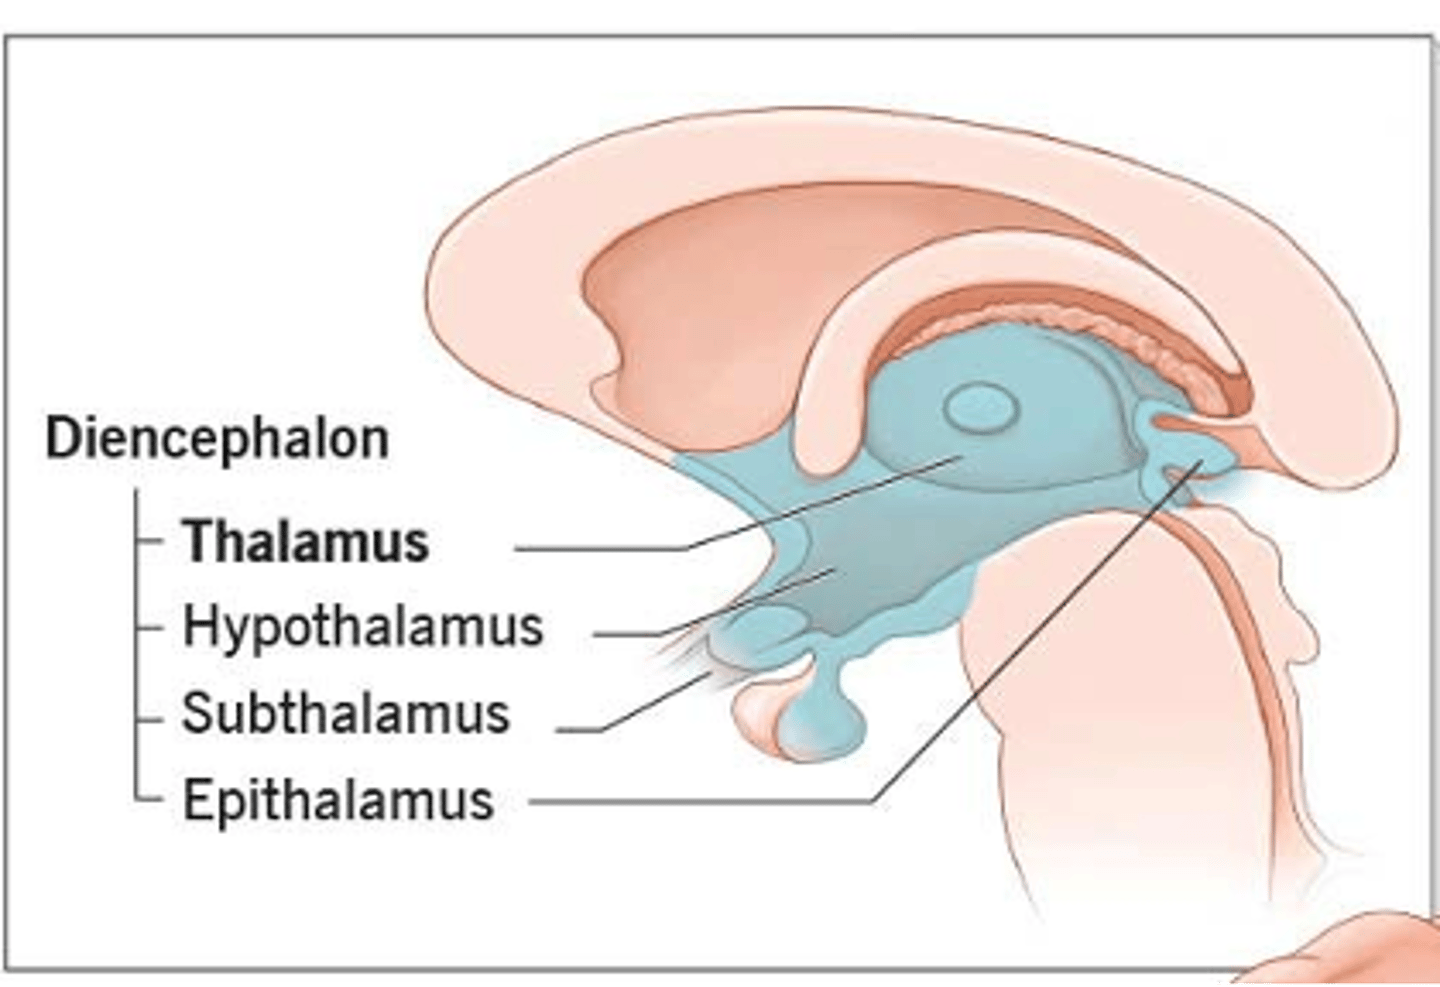

what are 2 important structures of the diencephalon?

1. thalamus

2. hypothalamus

what structure of the diencephalon regulates the of flow sensory and motor information from various location that will ultimately reach the cortex?

thalamus

what structure of the diencephalon is the relay station for all but one sensory tracts on their way to the cortex? what is the exception?

thalamus

olfactory is the only tract to bypass the thalamus and go directly to the cortex

what are 2 key thalamic nuclei?

1. ventral posterolateral nucleus (VPL)

2. ventral posteromedial nucleus (VPM)

what structure of the diencephalon is the main visceral control center of the brain?

hypothalamus

what structure of the diencephalon mediates a wide range of functions through connections with endocrine, autonomic, somatic motor, limbic systems, and maintaining a state of homeostasis?

hypothalamus